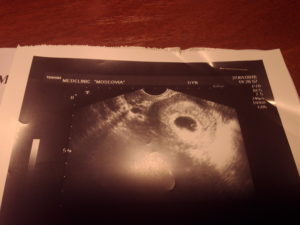

При трансвагинальном исследовании датчик вводят непосредственно во влагалище. Это позволяет получить наиболее точные результаты даже на самых ранних сроках.

Слишком малые размеры зародыша не позволяют сделать точную оценку его положения при обычном сканировании. Необходимо, чтобы датчик располагался как можно ближе к плодному яйцу. А это можно сделать именно при трансвагинальном ультразвуке, поэтому при ЭКО такой способ рекомендуют на самом первом исследовании.

2. Трансвагинальное исследование. В этом случае ультразвуковой датчик вводится непосредственно во влагалище. Рекомендуется проводить такую процедуру на начальных сроках беременности. Ведь эмбрион в этом периоде имеет очень малые размеры, и его очень трудно разглядеть при помощи обычного способа.

Кроме того, при таком способе исследования можно подробно рассмотреть и шейку матки.

Для первого УЗИ используется только трансвагинальное исследование. Это связано с тем, что врач должен подробно рассмотреть зародыш, а также его расположение. Такой способ исследования крайне важен для повышения точности диагностики. В последующем врач может повторить трансвагинальное исследование, а в дальнейшем – делать только трансабдоминальное.